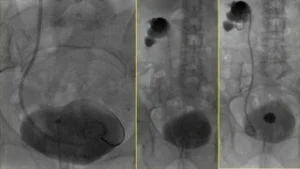

La nefrostomia è una procedura in cui viene posizionato un drenaggio percutaneo attraverso la pelle per drenare l’urina direttamente dal rene verso l’esterno. Questa procedura viene eseguita sotto guida radiologica, in cui il radiologo interventista punta il calice renale e inserisce il drenaggio. È spesso necessaria in caso di danni traumatici o iatrogeni delle vie urinarie, oppure per “mettere a riposo” la via escretrice in caso di ostruzioni gravi.

Stent Pielo-Vescicale

In alcuni casi, per preservare la pervietà dell’uretere e favorire la rapida cicatrizzazione, viene posizionato uno stent pielo-vescicale. Questo stent aiuta a mantenere l’uretere aperto e ridurre il rischio di recidive. Può essere posizionato per evitare il discomfort di un drenaggio esterno, ed è indicato quando si vuole conservare il comfort del paziente.

Posizionamento di Stent Nefro-Vescicale

In alcuni casi, viene posizionato uno stent nefro-vescicale quando il drenaggio esterno non è più necessario o desiderato dal paziente. Questo stent può essere posizionato anche in urgenza, ad esempio in presenza di infezioni gravi, insufficienza renale acuta o in pazienti con un solo rene. La sostituzione periodica degli stent può essere eseguita endoscopicamente dall’urologo o sotto guida radiologica dal radiologo interventista, con una procedura rapida e a basso rischio in regime di day surgery.